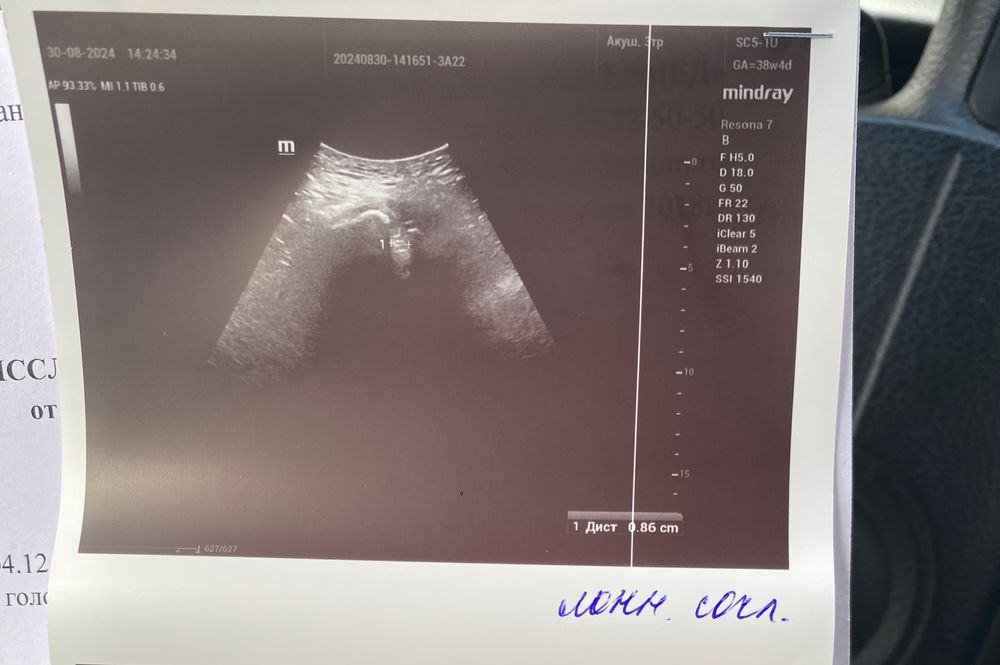

так же делала узи лонного сочленения, из за сильных болей. Не могу вставать, переворачиваться и хожу с трудом , намерили 9 мм расхождение

вес на узи 4100, а расхождение сказали 5 мм. Не понимаю теперь кто ошибся